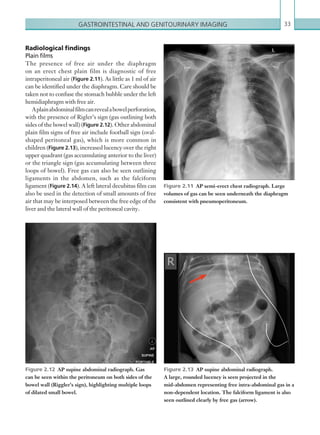

Figure 1.13  PA chest radiograph. Area of peripheral

consolidation at the left mid zone representing an area

of peripheral lung infarction.

Figure 1.14  Axial image: IV contrast enhanced

CT scan of the pulmonary trunk in the arterial phase.

There are features of chronic pulmonary emboli with

recannalised embolic material seen along the walls of the

right main pulmonary artery (arrow).

Figure 1.15  Axial image: IV contrast enhanced

CT pulmonary angiogram. The diameter of the main

pulmonary trunk is greater than the diameter of the

ascending aorta at that same level, suggesting pulmonary

hypertension. The cause is chronic pulmonary emboli

completely occluding the right main pulmonary artery.

Figure 1.16  Axial image: IV contrast enhanced

CT scan of the thorax in the arterial phase. Mosaic

attenuation of the right upper lobe is shown as a result

of abnormal pulmonary perfusion in chronic embolic

disease.